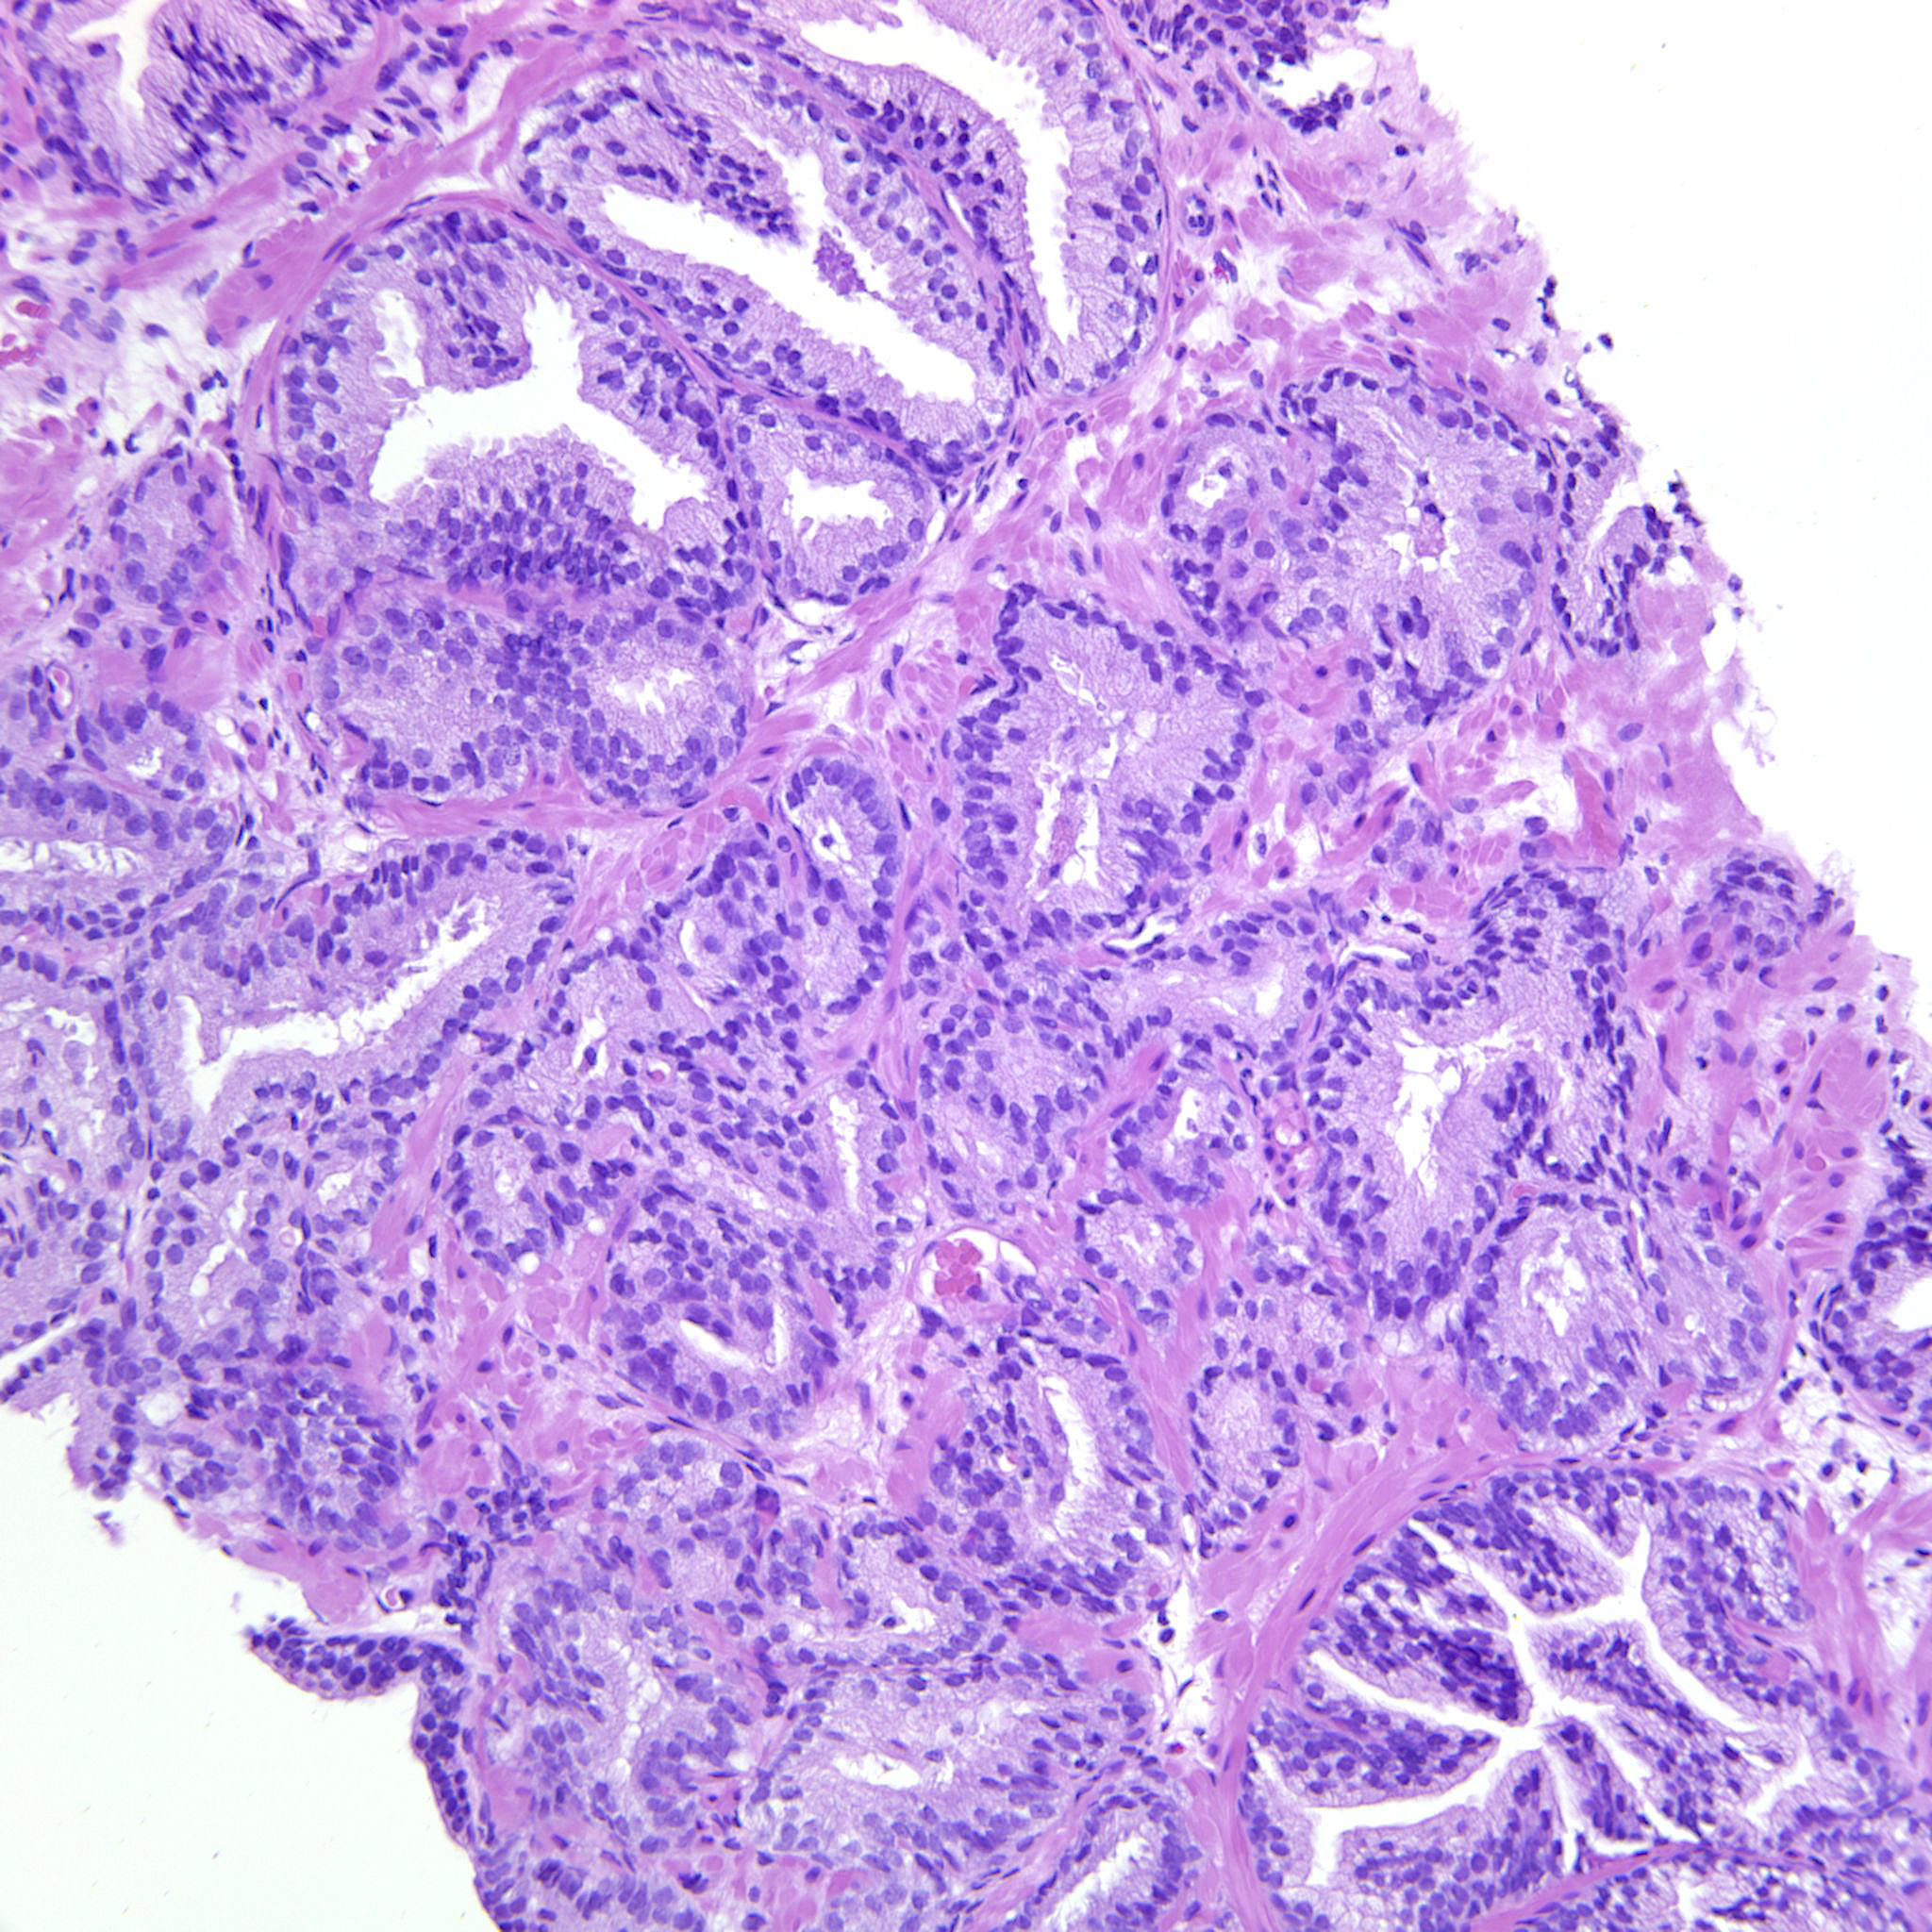

Prostate cancer grading

Case ID: 738